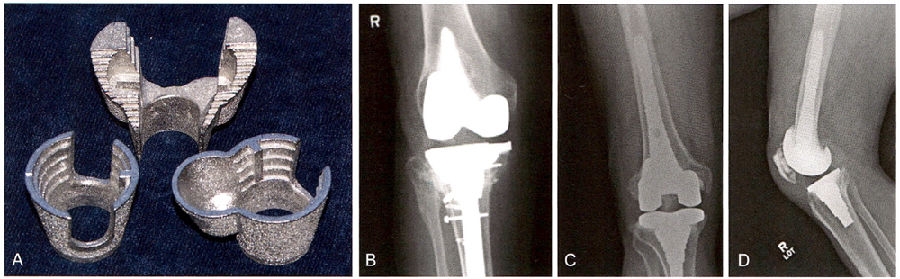

尽管目前在初次置换中常常作为非必要部分多孔金属加强块和锥形袖套的报道应用的效果较好(图5A)。把锥形袖套压配到股骨远端或胫骨近端的包容性骨缺损中,并用骨水泥把假体粘贴于这些加强块上使其成为一体。还可以把锥形袖套和假体组合形成一体式的假体结构。包容性骨缺损中,锥形袖套也可以粘在假体上组合形成单一假体结构。诸如图5B和C。这些方法大部分应用于伴有明显骨缺损的翻修手术中。这些锥形袖套的骨整合能力非常好,甚至假体失败后也很难取出。

图5 A.将多孔金属锥体放置在干骺端缺损处,以加强固定。B.此X线片示用双叶胫骨假体扩大由于胫骨平台骨折不愈合造成的缺损。C.如图所示,类风湿关节炎骨不良患者翻修TKA的正侧位片中,与植入物茎端相连的袖套型假体可以增强骺端包容或非包容性的缺损